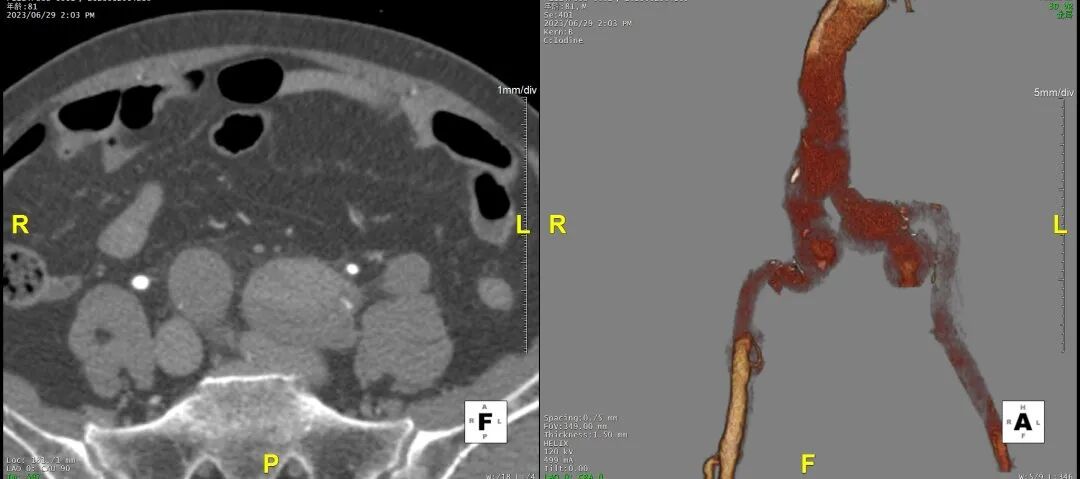

3D影像

1)内膜多处撕裂,真腔严重狭窄。

2)CA假腔供血,SMA双腔供血,LRA假腔供血,RRA真腔供血,腹主段闭塞。

3)LSA起始部平均直径43mm+,降主段多发破口,真腔狭窄。